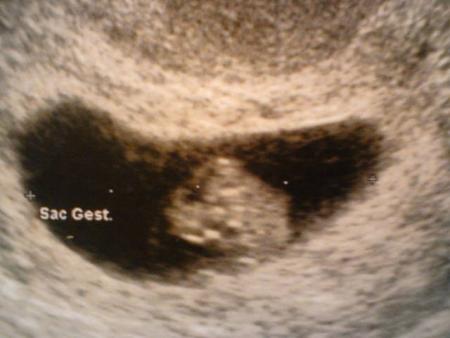

Et là le moment magique, l'écho : bébé va bien, il n'y en a qu'un mais en pleine forme !!!

Il mesure 13.9mm, on voit son coeur et son cerveau en plein fonctionnement, trop beau !!!

Sur la photo de l'écho le noir c'est le sac gestationnel, donc la piscine privée de bébé et la tâche blanche au milieu c'est bébé :) la "boule" du dessus c'est sa grosse tête !!!